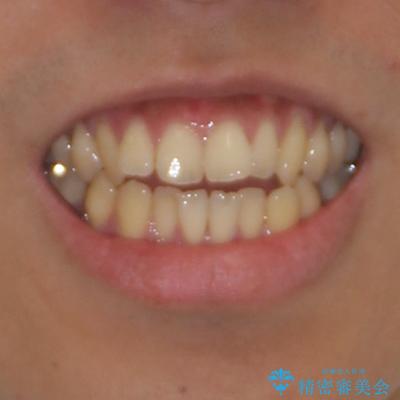

隙間が空いて突出した前歯を治したい ワイヤー装置による抜歯矯正

- 上下前歯の隙間と口元の出っ張った感じを気にして来院された患者様です。

上下の隙間は舌突出癖によるもので、またその癖により前歯が前方に出ている状態でした。

口元の出っ張りを改善するため、上下左右第一小臼歯4本を抜去し、ワイヤー装置にて矯正治療を行うこととしました。